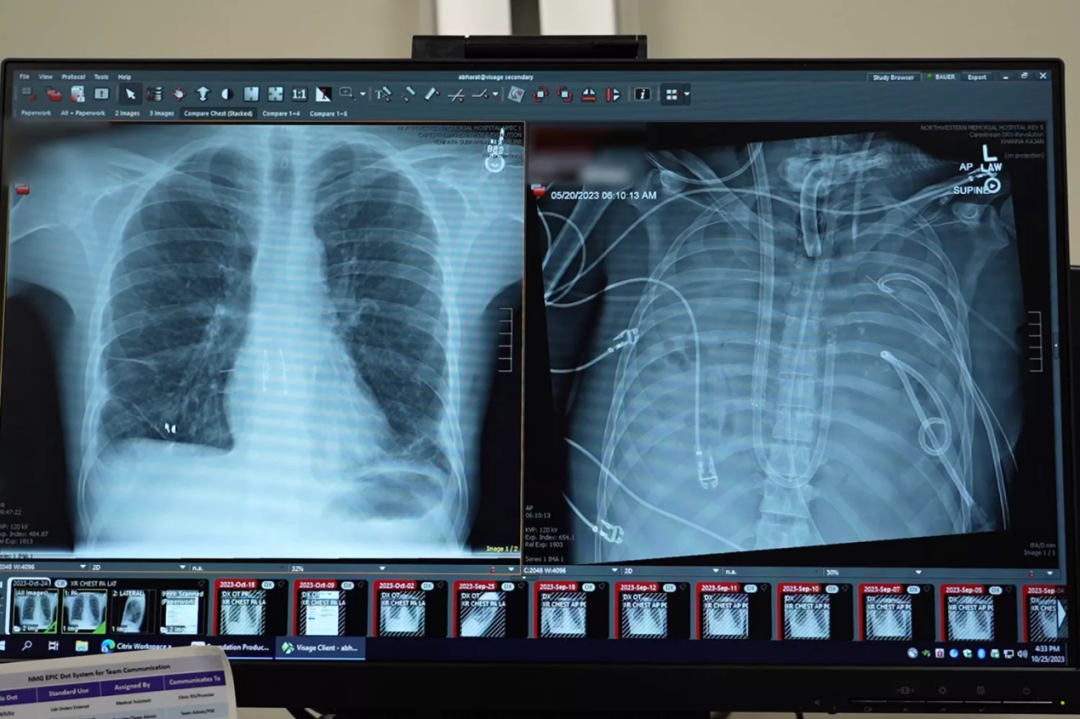

戴維雙肺移植前(左)後(右)的影像學檢查結果。圖源/Northwestern Medicine